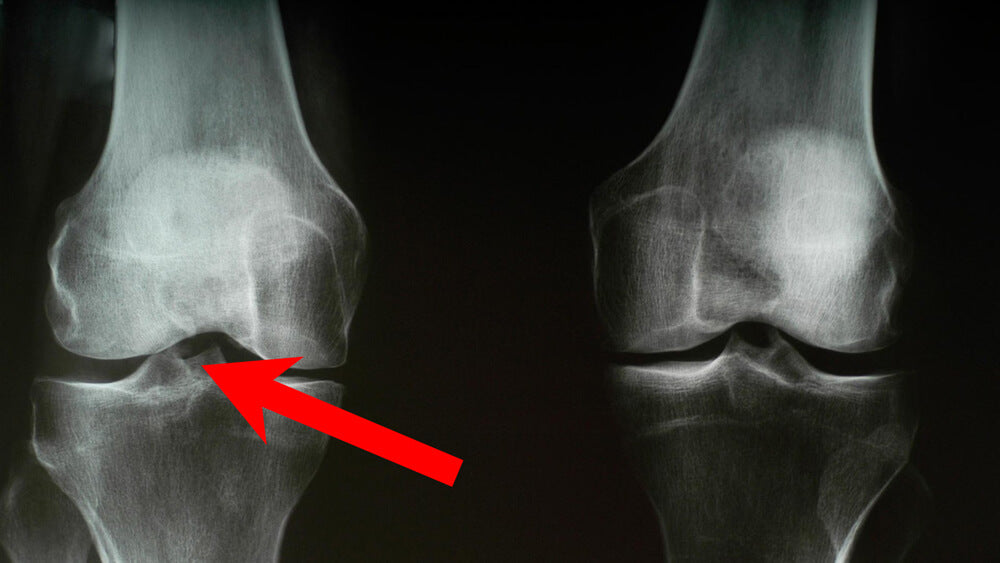

Zwischen allen Gelenken befinden sich Knorpel, welche die Gelenke schützen.

Diese Knorpel werden über die Gelenkflüssigkeit mit Nährstoffen versorgt.

Wenn die Knorpel zu wenig Gelenkflüssigkeit erhalten, trocknen sie aus und werden brüchig.

Dies führt dazu, dass sich die Knorpelpuffer zwischen den Gelenken abbauen.

Die Knorpel können die Gelenke daraufhin nicht mehr ausreichend schützen und die Gelenkknochen reiben aufeinander.

Die Folge: Die Gelenke entzünden sich.

Das kann wiederum zu starken Schmerzen führen.

Knorpelschäden entstehen und es kommt zu Arthrose.